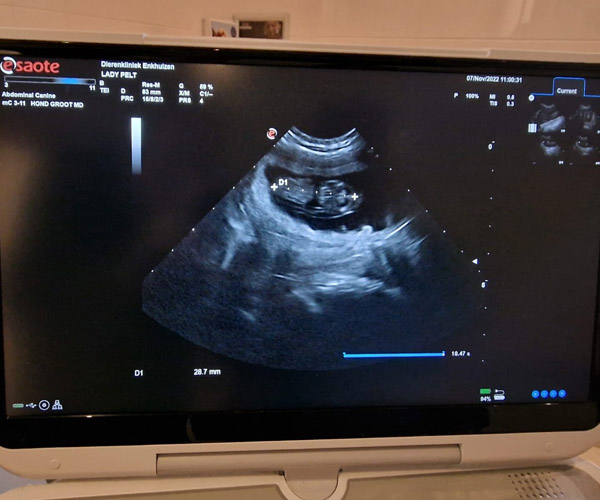

Maandag 7 november: YES YES YES YES Lady verwacht puppen! De dierenarts heeft het bevestigd door middel van een echo. We hadden al goede hoop omdat Lady zelf heel erg laat zien dat ze meer wil rusten en minder wil spelen en ze wil echt meer eten. We zijn zo ontzettend nieuwsgierig of ze dan puppen krijgt van beide vaders. En of we al aan de puppen kunnen denken te herkennen of ie van Twix of van Rumi is. We zullen daarin ons geduld moeten bewaren tot de Raad van Beheer DNA van de puppen heeft afgenomen (dmv een wattenstaafje door hun bekje te halen) en ons de uitslag te geven. Nu eerst hopen op een fijne dracht en een voorspoedige bevalling.